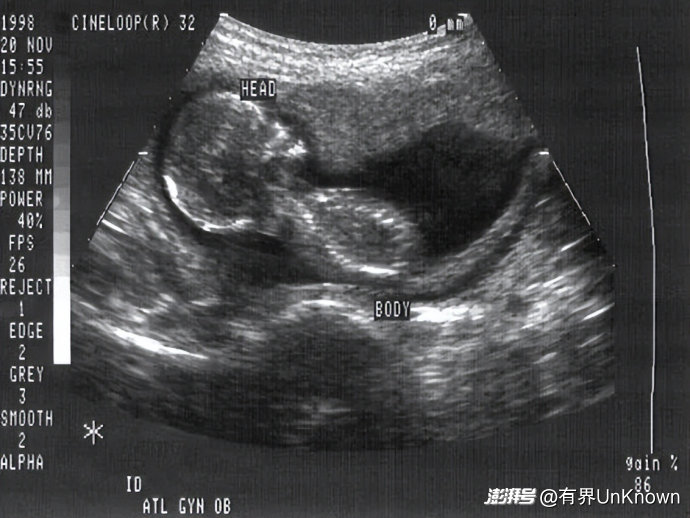

▲ 孕妇怀孕期间的B超图像